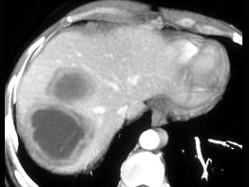

男,41岁,发热、右季肋部疼痛十余天.请根据CT图像,选择最可能的诊断 ( )A、肝囊肿B、肝包虫病C、阿米巴肝脓肿D、肝结核E、肝癌

问题 男,41岁,发热、右季肋部疼痛十余天.请根据CT图像,选择最可能的诊断 ( )

选项 A、肝囊肿 B、肝包虫病 C、阿米巴肝脓肿 D、肝结核 E、肝癌

答案 C